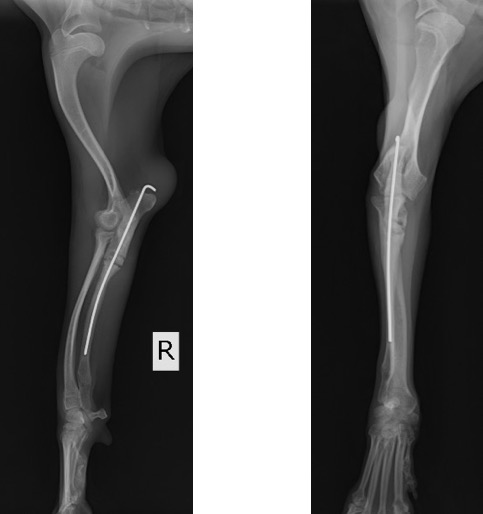

術前計画としてCT検査を実施し、肘関節の整合性を確認した後に、橈骨の湾曲防止と肘関節の不整合を矯正するために尺骨の骨切術を実施しました。

術後のLateral像とAP像 (骨切り後に尺骨のアラインメントを合わせるために髄内ピンとして1.2mm K-wireを刺入しました)